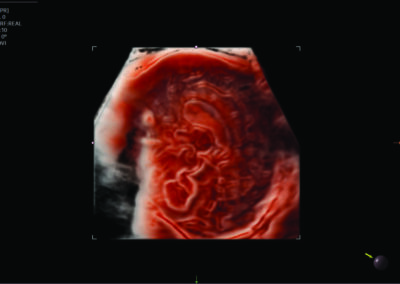

Comprehensive, advanced and expert MFM care for high-risk pregnancies